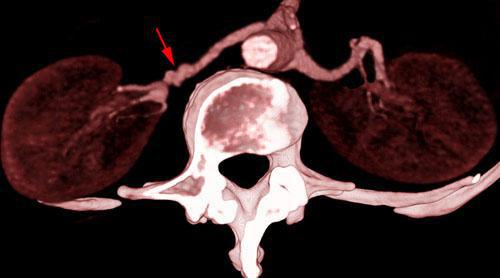

Estenosis por displasia fibromuscular de arterias renales

VR 3D Visión caudal. AngioTC renal mostrando estenosis concéntricas (flecha) en el tercio medio de la arteria renal derecha